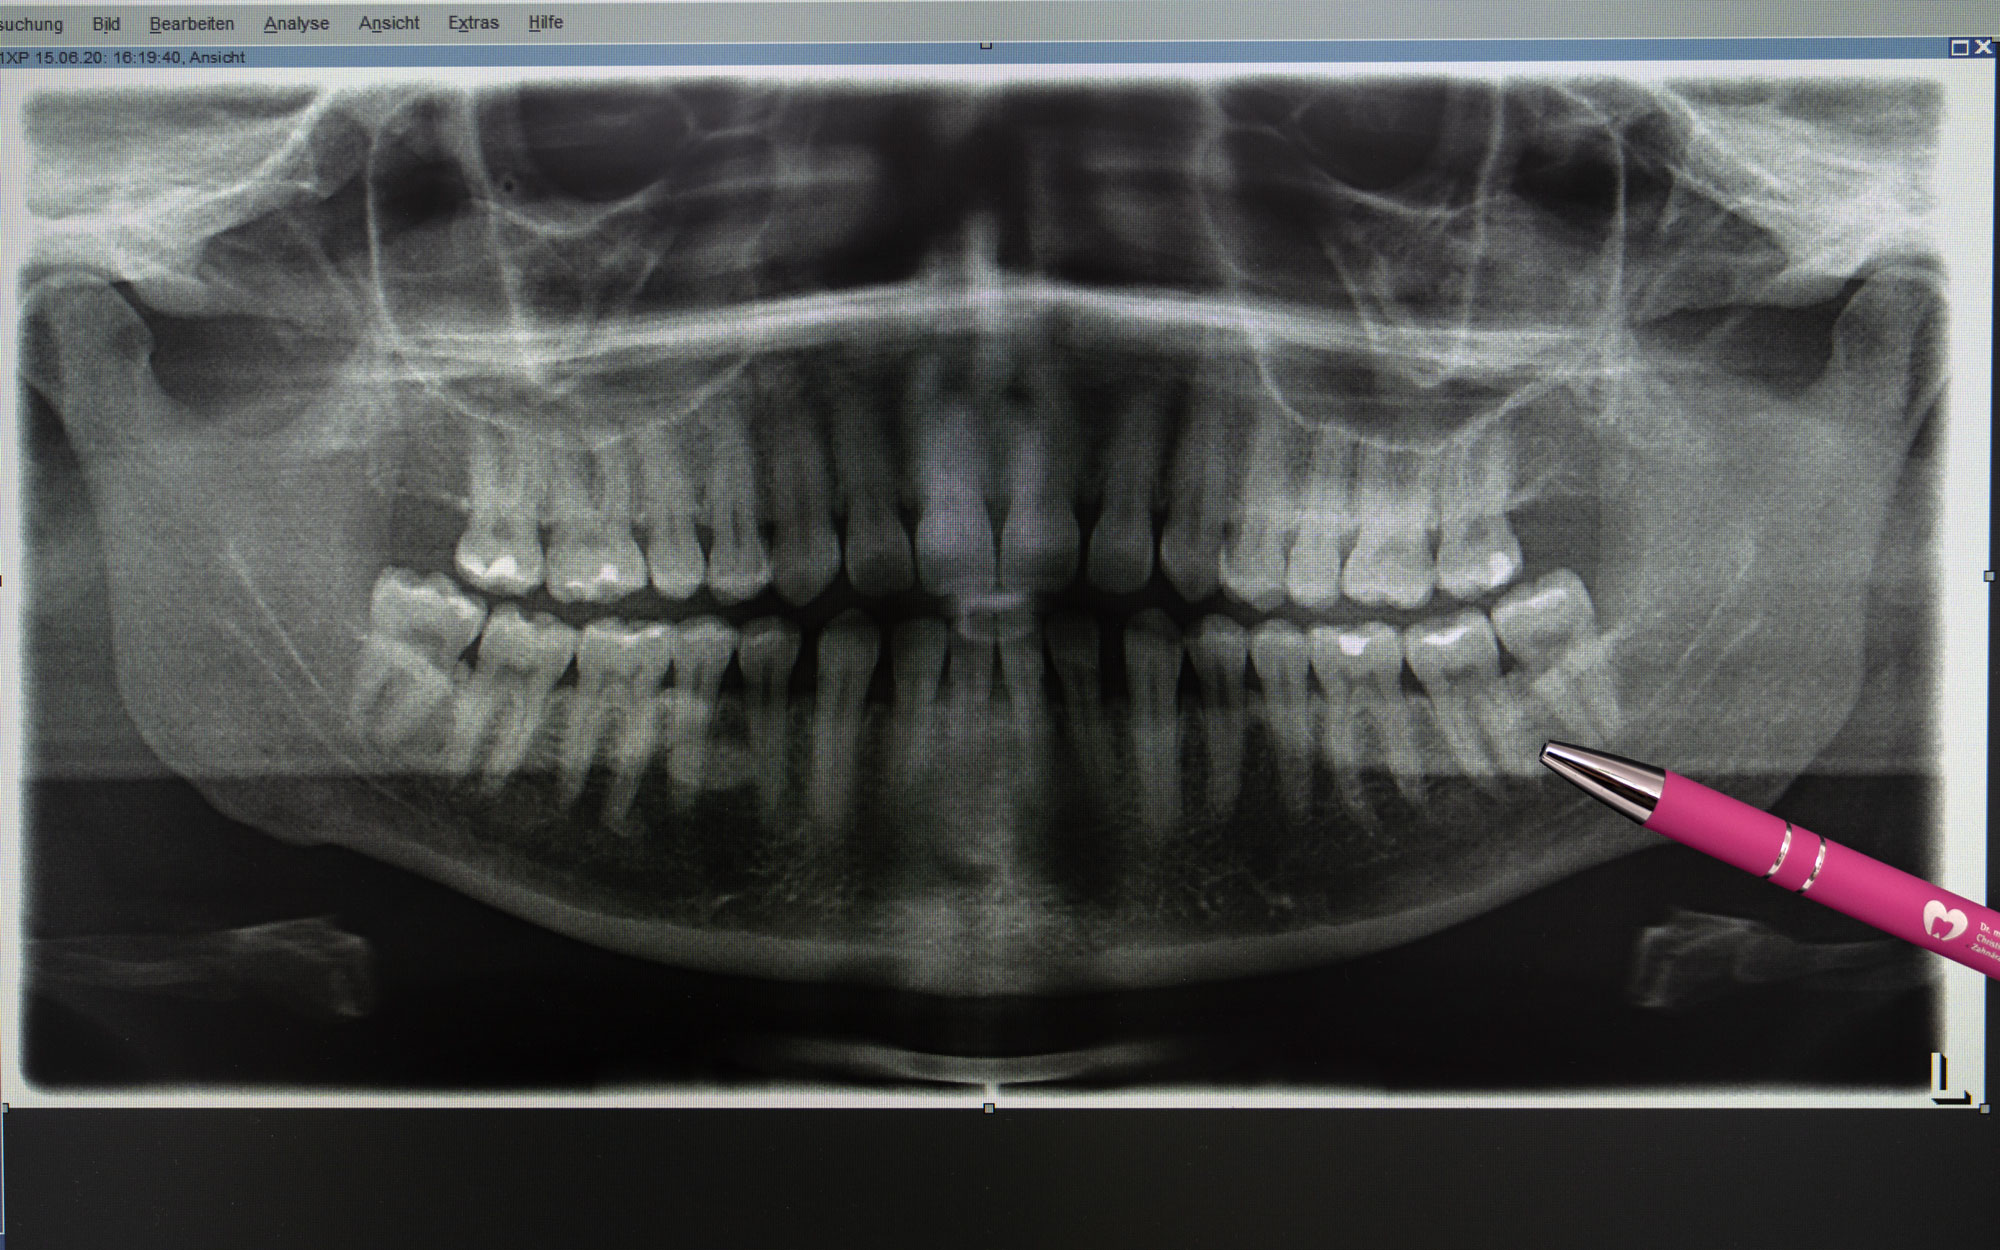

Die festsitzende Zahnversorgung, wie zum Beispiel Brücken, Kronen

Bei größeren Defekten und einzelner fehlender Zähne, kann festsitzender Zahnersatz in Form von Kronen und Brücken notwendig werden.